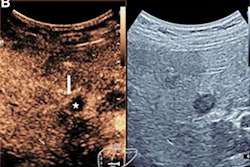

Sentinel lymph nodes can be identified through contrast-enhanced ultrasound lymphosonography (pictured), rivaling that of blue dye and radioactive tracers, according to research presented at the RSNA annual meeting. Image courtesy of Dr. Priscilla Machado.Comparison with the blue dye reference standard showed that lymphosonography had 73% accuracy while the radioactive tracer's accuracy was 72%, although this did not achieve statistical significance.